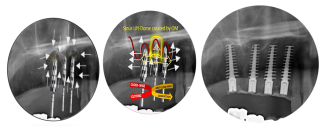

OM Sinus lift; resulting in Dome created by Osseo-Manipulation along with compaction, condensation and lift

Osseo-Manipulation – The “C” Principal:

- Clockwise: Careful Characteristic Controlled Cutting

Utilizes precise techniques to minimize bone removal

- Counter-Clockwise: Comprehensive Consistent Cyclic Compaction

Ensures consistent and thorough compaction in a cyclic manner to enhance structural integrity.

- Creating: Continuous Consolidated Condensed Concentration Configuration

Maintains a continuous focus on consolidating and condensing components into an optimized configuration.

The osseo-manipulation tapered drills protocol: